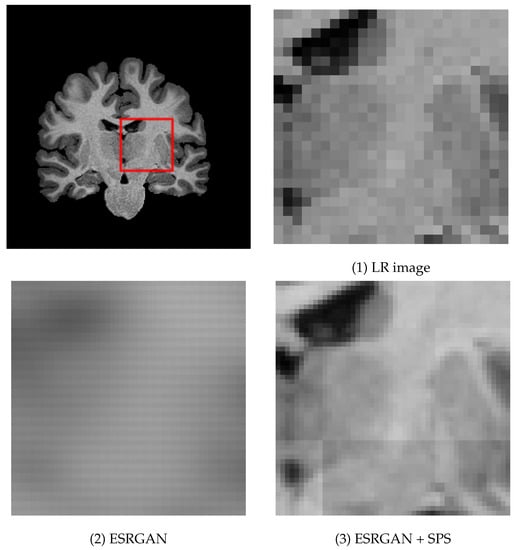

Figure 2 and Figure 3 show examples of MR images generated by proposed super-resolution networks and their original HR images, and their magnified view, respectively. In Table 1, the average SSIM and PSNR between super-resolved images using each method and their ground-truth high-resolution images are also summarized.

Figure 2.

Examples of generated images with their input and ground-truth images. (1) low-resolution input image, (2) ESRGAN without SPS and ASD, (3) ESRGAN + SPS, (4) ESRGAN + SPS + ASD (proposed), and (5) ground truth high-resolution image.

Figure 3.

Magnified example of the the generated image.

The output images of the network without SPS, i.e., plain ESRGAN (column (2)), are visibly blurry, and most of the structural features are lost, leading to the lower SSIM/PSNR value. With the proposed SPS (column (3)), generated images are significantly sharper and visibly natural-looking. However, grid-shaped intensity shifts appear at the joints of each patch (Figure 3 (3)). On the other hand, almost all the intensity shifts are suppressed with the images with the proposed discriminator (column (4)).